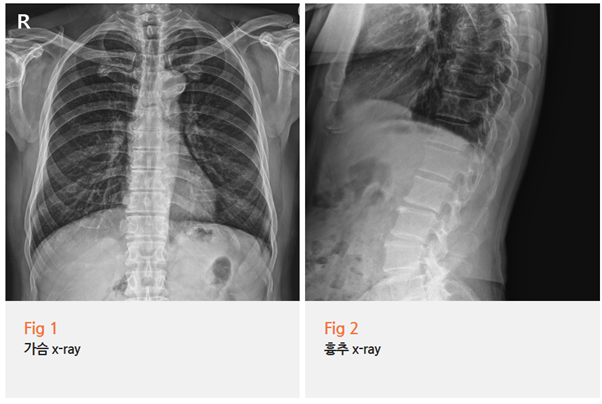

바로 X-ray 촬영을 했습니다.

그리고 환자분을 직접 진찰해보니...

아, 맞네요.

늑간신경통이었어요.

그림10.png 촬영 일시: 2025.08.01

갈비뼈 사이를 따라 지나가는

늑간신경에 문제가 생긴 거였습니다.